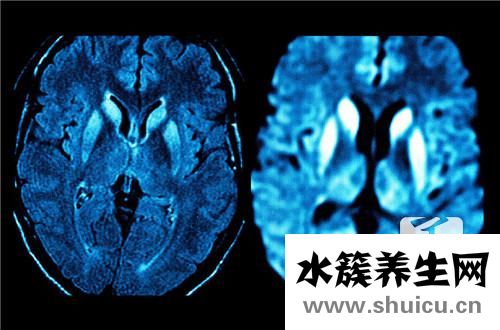

成人缺氧缺血性腦病可能是由多種因素引起的腦損傷性疾病。 特別是高強度的腦力勞動者,或者在低氧空調房間中長期居住的白領工人很容易引起這種疾病。...